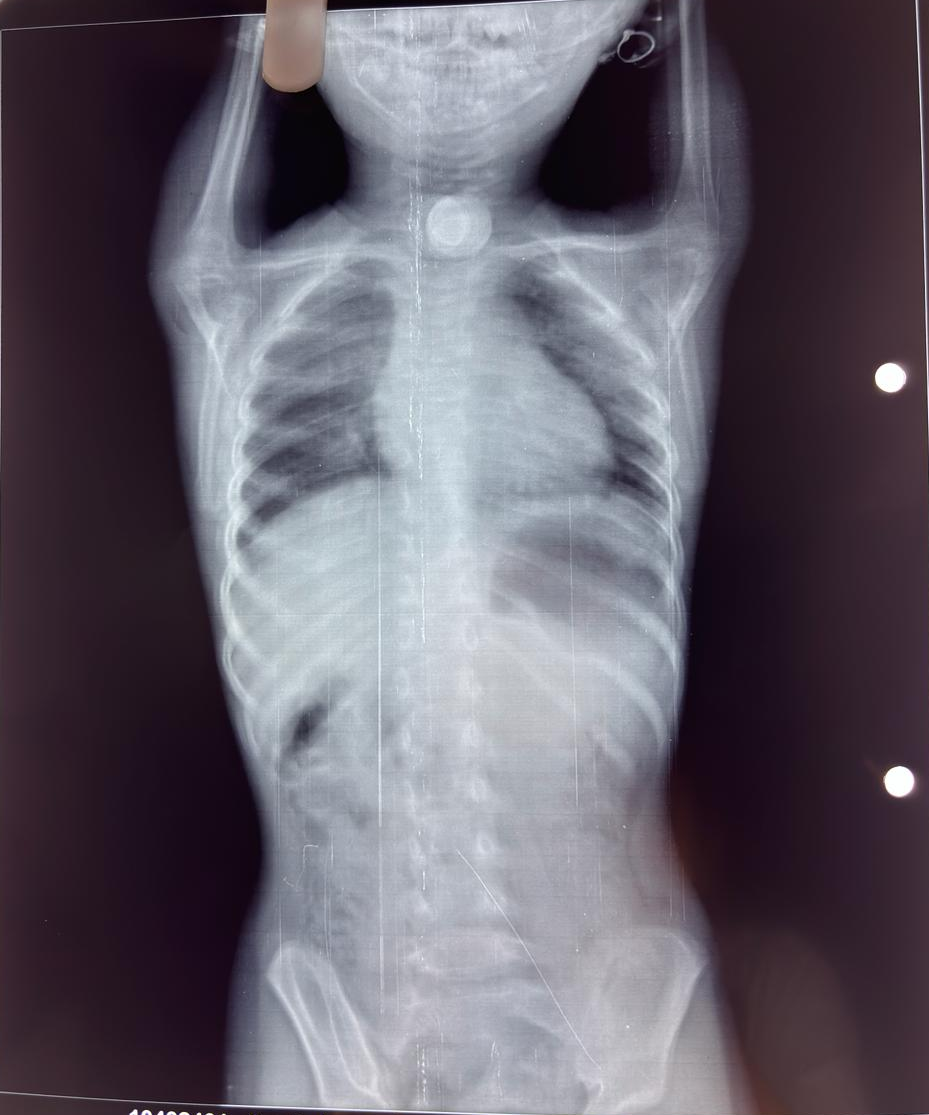

Throat Surgery near me Throat Surgery in Nagpur Th...